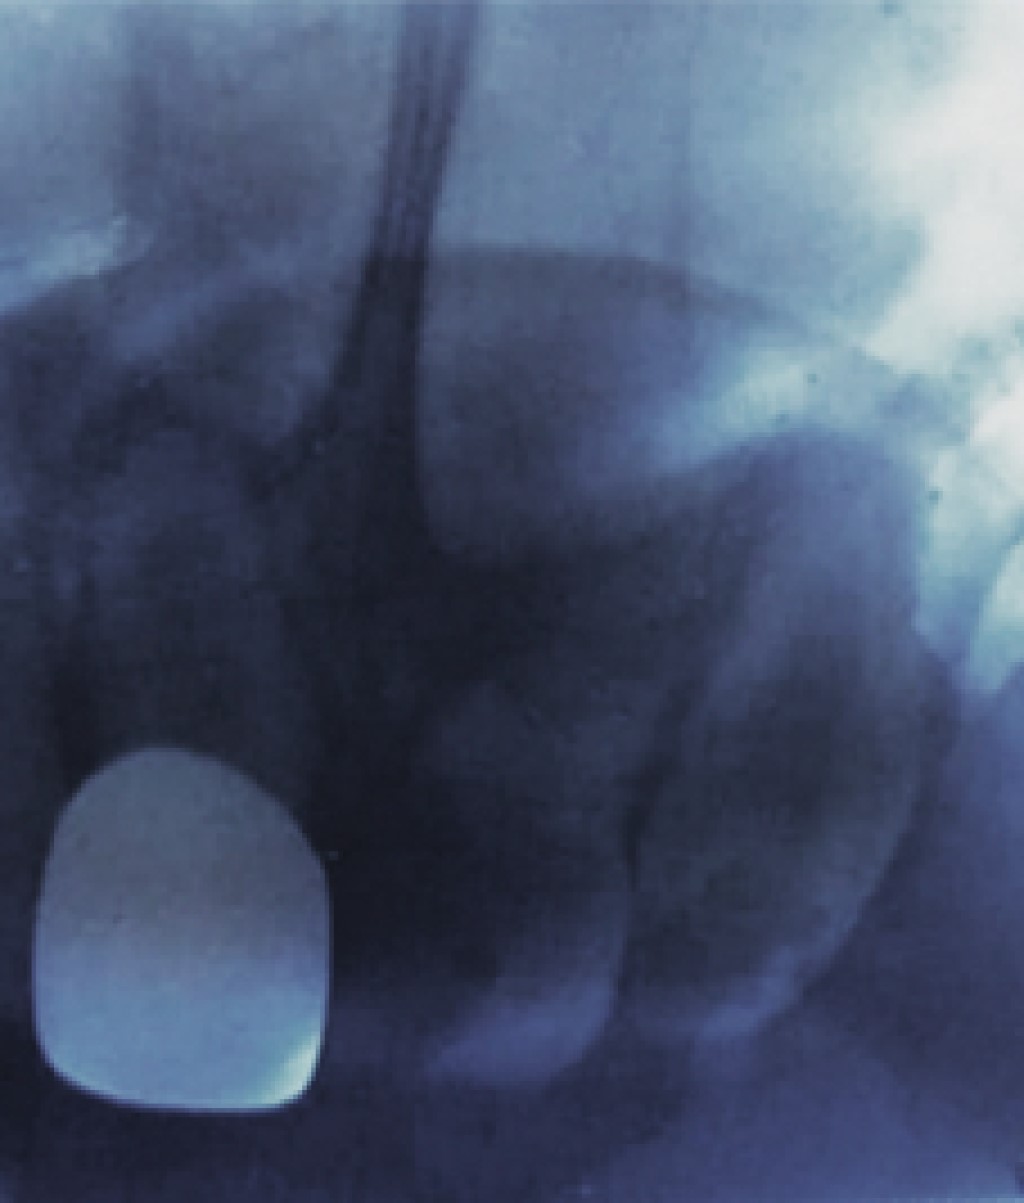

Al hacer una valoración radiográfica, se observa ausenscia de tratamiento de conductos en el OD 51, así como reabsorción interna radicular en el OD 61, zona radiolúcida comprometiendo cámara pulpar y evidente pérdida de estructura coronal (Figura 2), por lo que se decide extraer el órgano dental como única alternativa de tratamiento.

Figura 2